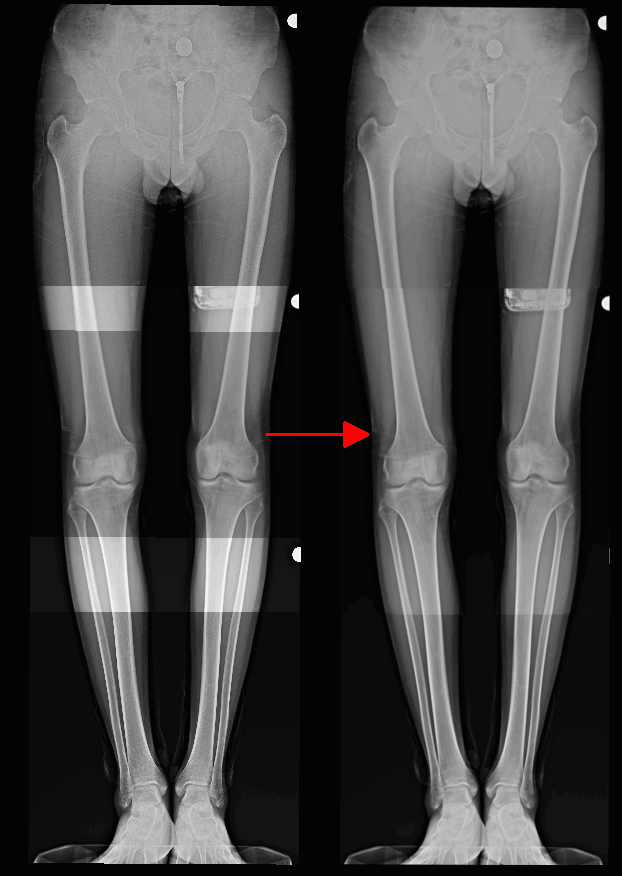

Stitching provides an opportunity to combine several images in a single panorama. To use the stitching mode, proceed as follows:

Merge the images in the Stitching view window manually (see Section 2.22.4) or automatically (see Section 2.22.5).

Click the arrow on the right-hand side of the Stitching mode

button on the image

stitching functional toolbar and select one of the stitching options. The selected

stitching option will be used by default each time you click the Stitching mode

button.

Cut overlapped. The intensity value in the area of overlap is set equal to the intensity value of the image whose position number is smaller. This option is checked by default as the default stitching option;

Mix overlapped. The intensity value in the area of overlap is set as the mean intensity value for all the overlapping images.

Click the Stitching mode

button on the image stitching functional toolbar. The image

in the Stitching view window will look similar to Fig. 2.67 (on the left, you can see the

merged images before stitching, on the right — after stitching).